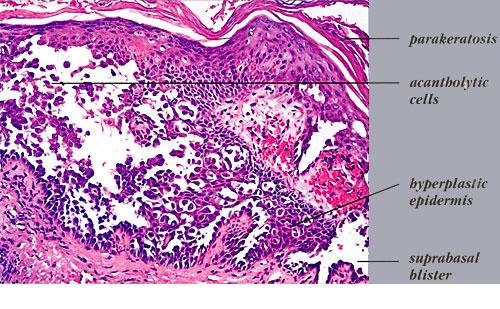

Although, as in Darier's disease, early lesions may show small suprabasal separations, so-called lacunae, fully developed lesions show large separations, that is, vesicles and even bullae, in a predominantly suprabasal position . Villi, which are elongated papillae lined by a single layer of basal cells, protrude upward into the bulla, and in some cases,

narrow strands of epidermal cells proliferate downward into the dermis. Many cells of the detached stratum malpighii show loss of their intercellular bridges; thus, acantholysis affects large portions of the epidermis.

Individual cells and groups of cells usually are seen in large numbers in the bulla cavity. Despite the extensive loss of intercellular bridges, the cells of the detached epidermis in many places show only slight separation from one another, because a few intact intercellular bridges still hold them loosely together. This quite typical feature gives the detached epidermis the appearance of a dilapidated brick wall.

Pemphigus vulgaris often resembles familial benign pemphigus to a striking degree, and in some specimens, histologic differentiation of these two diseases may be impossible. As a rule, however, there is less extensive acantholysis in pemphigus vulgaris, limited largely to the suprabasal region, so the detached epidermis appears normal and lacks the appearance of a dilapidated brick wall, and more severe degeneration of the acantholytic cells within and near the bulla cavity. The presence of eosinophils in the bulla points toward a diagnosis of pemphigus vulgaris, but their absence does not rule it out. In case of doubt, immunofluorescence will decide the issue.

Histologically, familial benign pemphigus shares certain features with both Darier's disease and pemphigus vulgaris. In all three diseases, one finds predominantly suprabasal separation of the epidermis caused by acantholysis and resulting in lacunae or bullae and villi formation.